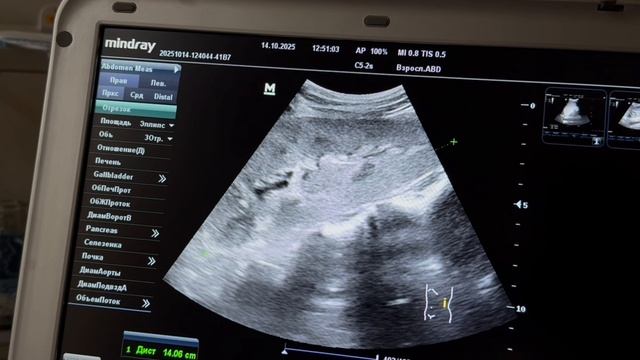

🏥 При выполнении протокола FAST (Focused Assessment with Sonography for Trauma) в условиях неотложной помощи 🚑, помимо очевидных находок, важно помнить ...